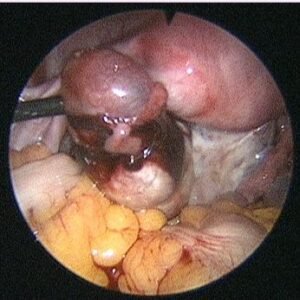

The diagnosis is also confirmed with ultrasound and blood flow studies (Doppler) during which the sac may be visualized in the region of the adnexa close to ovary. The treatment may be medical with methotrexate (chemotherapeutic agent) given either as oral medication or an injectable, depending on the combined laboratory and clinical findings. If surgical intervention is decided upon then laparoscopic surgery will be performed in most patients who are hemodynamically stable. In cases where the patient presents late with the symptoms or the pregnancy has ruptured with bleeding into the abdomen laparotomy (10%) is performed.

The affected tube is most often if not always removed after examining the opposite tube and assessing the patient’s chances of future conception. Even with one healthy tube it is possible to conceive. In our experience removal of tube almost always reduced chances of recurrence and helped improve pregnancy rates by either trying for conception with the opposite tube or with ART.